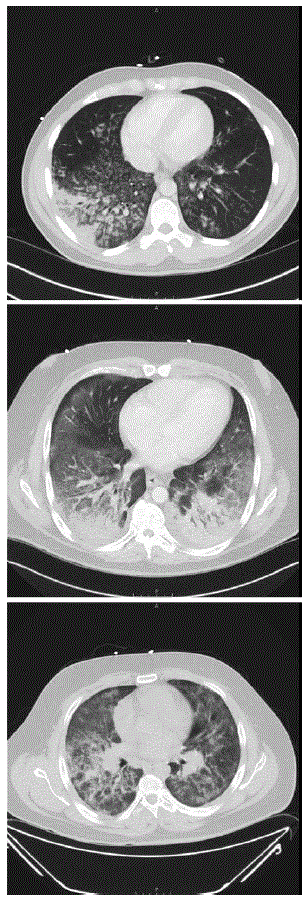

Computed tomography of the chest revealed diffuse basilar-predominant infiltrates with a range of “ground glass” opacities and nodular or “tree-in-bud” infiltrates in all patients (Figure 1). Three patients underwent bronchoscopy with bronchoalveolar lavage on hospital days 3–5, yielding a combination of neutrophils, lymphocytes, and vacuole-laden macrophages, but without evidence for alveolar hemorrhage or eosinophilia (Figure 2). No bronchoscopic lung biopsies were performed. Lavage cytology was stained with oil red O, which confirmed extensive lipid within alveolar macrophages (Figure 2). Based on clinical history, radiography, and laboratory and bronchoscopic diagnostics, a diagnosis of acute exogenous lipoid pneumonia was made for all five patients.

Return to your place in the textFIGURE 1. Computerized tomography images showing diffuse lung infiltrates in three patients with e-cigarette–associated severe lung disease — North Carolina, July–August 2019

The figure consists of three computerized tomography images showing diffuse lung infiltrates in three patients with e-cigarette–associated severe lung disease in North Carolina, during July–August 2019.